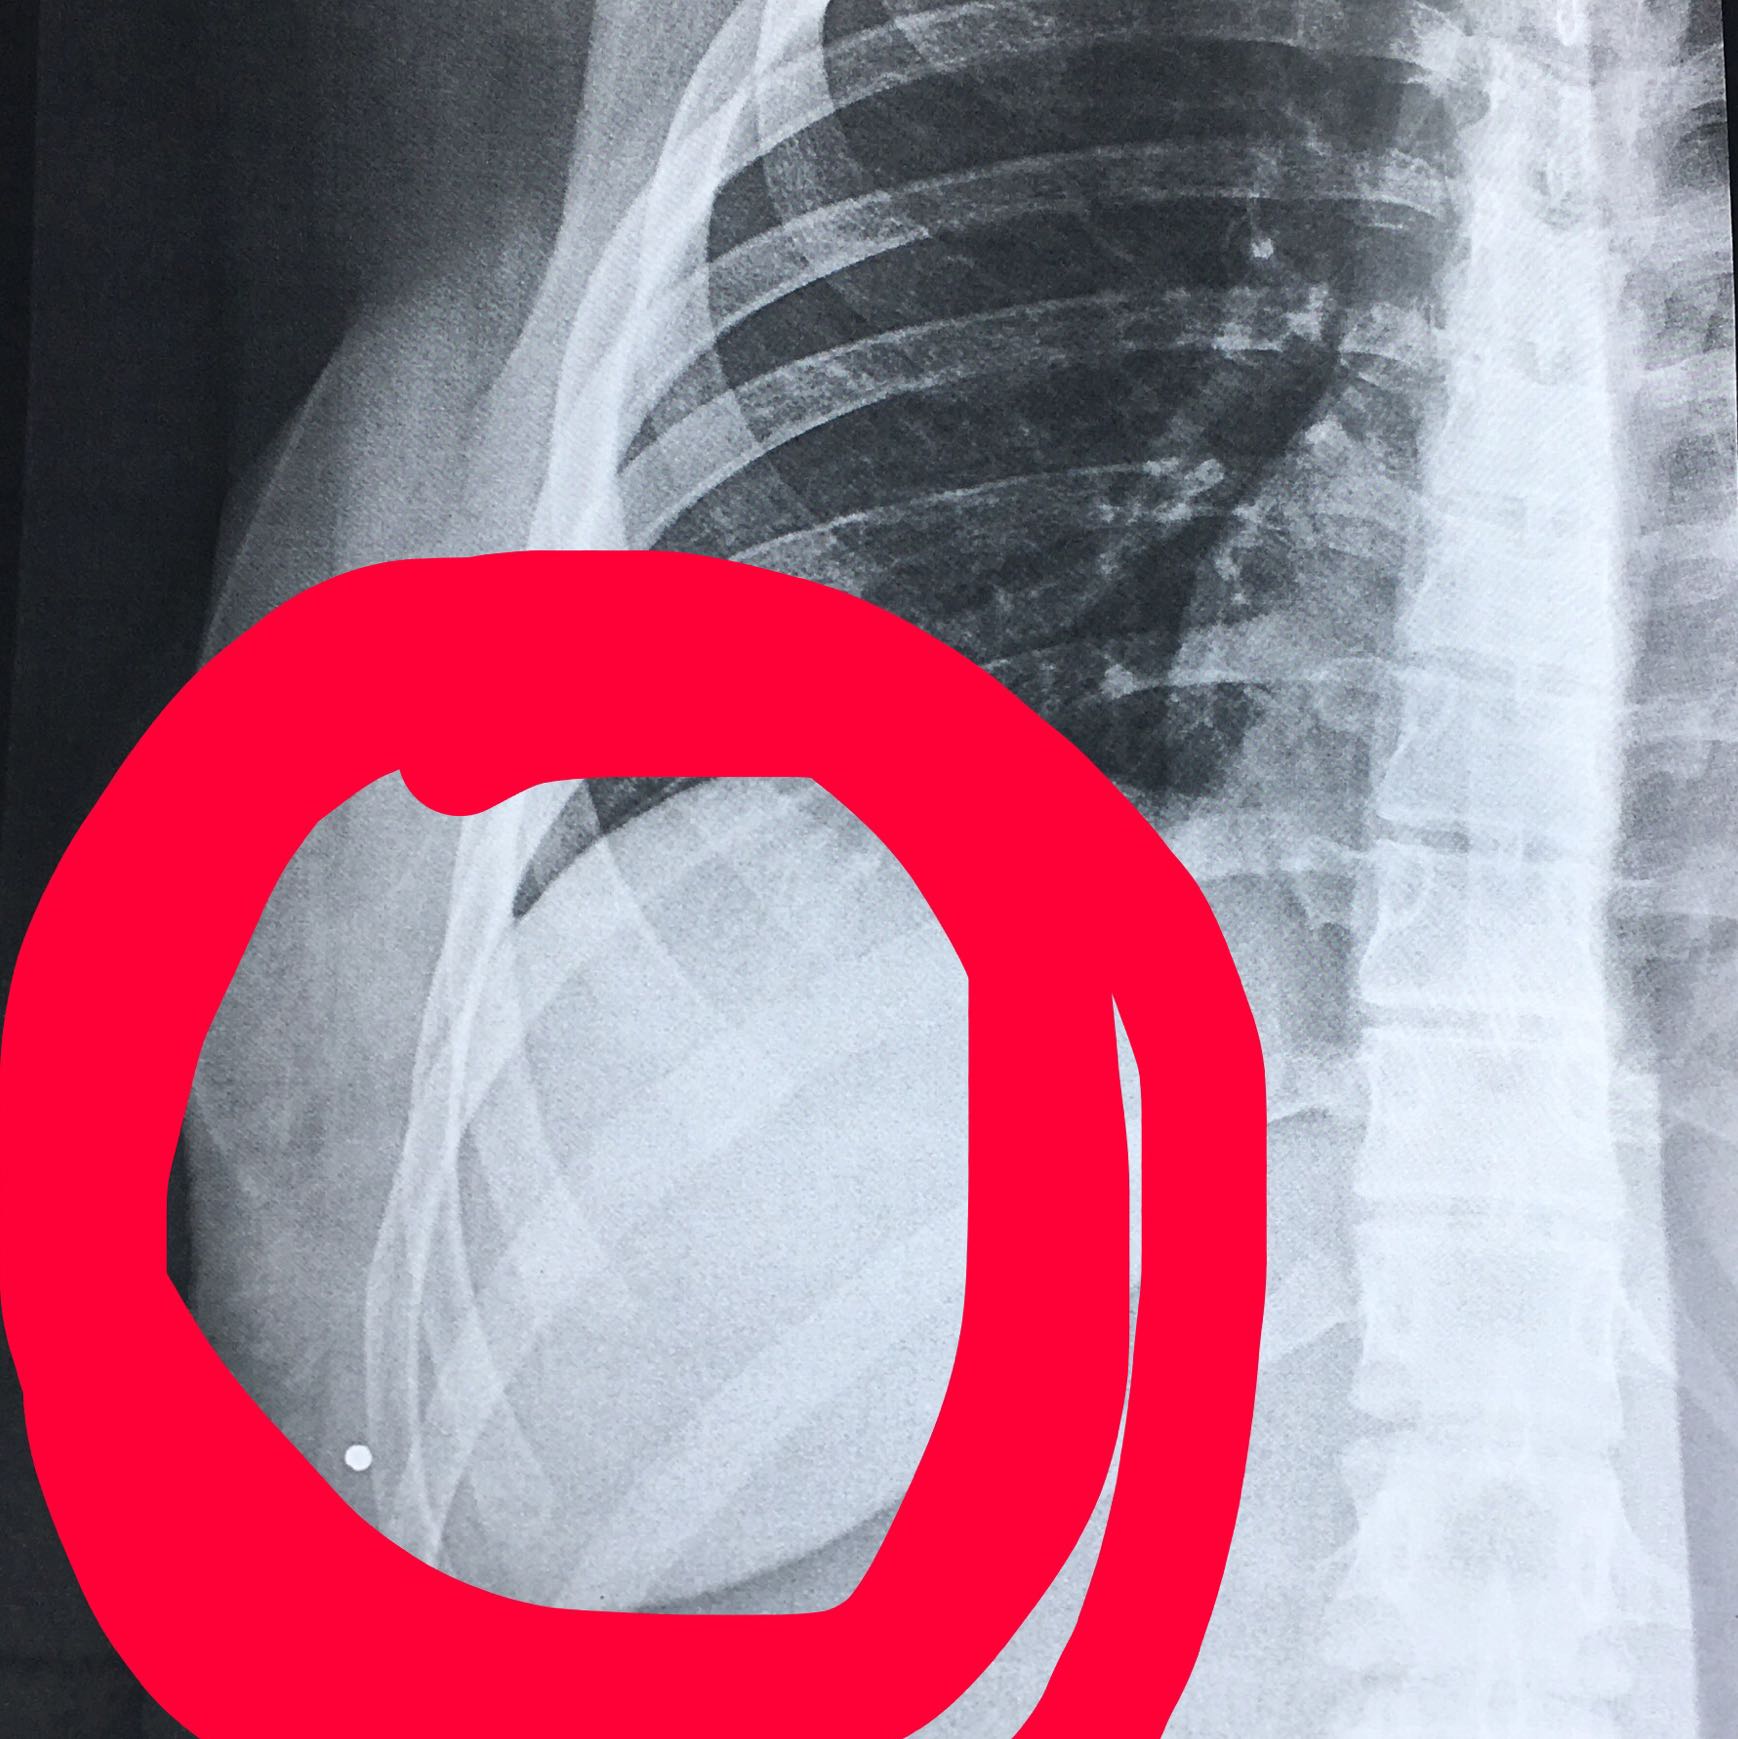

Rippe geprellt oder gebrochen. Eine Rippenprellung und ein -bruch haben prinzipiell dieselben Ursachen. Die Symptome der Rippenprellung unterscheiden sich im Grunde nicht von denen des Rippenbruchs. In schweren Fällen können die Schmerzen jedoch bis zu acht Wochen andauern.

Weiches Gewebe wie Muskulatur oder Unterhautfett wird gegen die Rippen gedrückt und gequetscht. Häufig verursacht die Prellung sogar stärkere Schmerzen als ein Rippenbruch und dauert länger an als ein Bruch. Schwere körperliche Tätigkeiten und sportliche Aktivitäten die die gebrochene Rippe gefährden sind in den ersten vier bis sechs Wochen nach dem Bruch im Regelfall Tabu.

Eine geprellte oder angeknackste Rippe ist zwar beschädigt aber noch an ihrem Platz im Brustkorb. Aufgrund der hoher Elastizität der Rippenknochen wird der knöcherne und knorpelige Anteil der Rippen häufig nur geprellt Rippenprellung. Geprellt gebrochen angebrochen.

Da die Rippen elastisch sind brechen sie eher selten. Der Rippenbruch Rippenfraktur ist die häufigste Verletzung des Brustkorbs. Rippenprellung oder Rippenbruch.

Die Rippen sind dabei nicht gebrochen. Bei stärkerer Gewalteinwirkung können eine oder mehrere Rippen brechen - in diesem Fall spricht man von einem Rippenbruch. Daher ist es ratsam einen Arzt aufzusuchen.